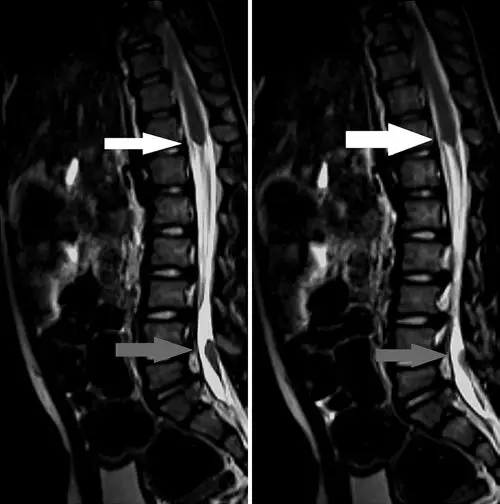

中枢神经系统胚胎发育发生在神经胚形成过程中,神经胚形成方式为初级神经胚形成(形成脑和脊髓,直至骶1-2交界处)和次级神经胚形成(形成1-2交界以下的脊髓节段)。连接型神经管缺陷(JNTD)是一种新报道的神经管闭合不全,发生于神经胚形成交界期(初级神经胚形成期结束与次级神经胚形成期开始之间),目前文献报告仅有4例,本病例为第5例,也是至今第1例伴终丝脂肪变的JNTD。患儿,男性,5岁,出生1月内接受过尿道直肠瘘手术,前来就诊评估是否合并神经管闭合不全。患儿有尿失禁、马蹄内翻足以及走路晚等病史。MRI显示脊髓分为两部分,上段止于T11水平,下段在L5-S1水平,合并终丝增粗。

胸腰椎MRI的矢状位T2加权像,显示脊髓的两个节段及其之间的连接组织。上段脊髓止于T11-12(白色箭头),下段脊髓位于L5-S1(灰色箭头)